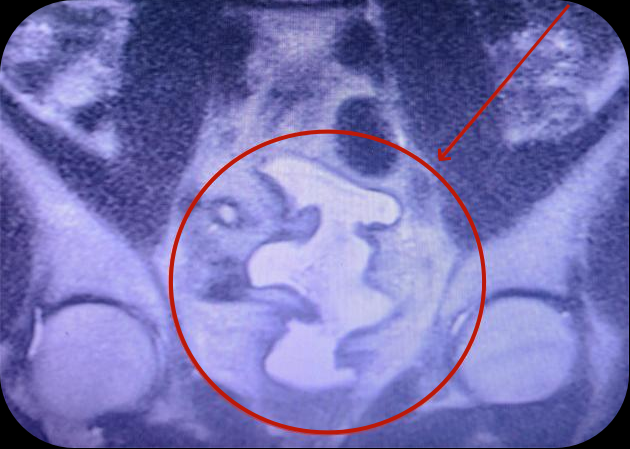

图中标识为膀胱扩大术后的膀胱

2022年底,贵州航天医院泌尿外科就完成了在遵义市首例全腹腔镜下乙状结肠膀胱扩大术,手术效果非常好。当时病例为24岁男性患者,两次排尿间隔仅十几分钟,且每次量很少,反复尿频1年以上就诊贵州航天医院泌尿外科,相关检查显示膀胱最大容量为12ml,被诊断为泌尿系结核、膀胱挛缩。随后,由李凯主刀,实施全腹腔镜下乙状结肠膀胱扩大术,截取肠管缝合成新膀胱,完成患者膀胱扩大术,新膀胱形态正常,无尿漏及其他并发症。

2名患者术后复查,肠道功能恢复良好,进食及排便均正常,排尿方面,尿频症状均明显改善。